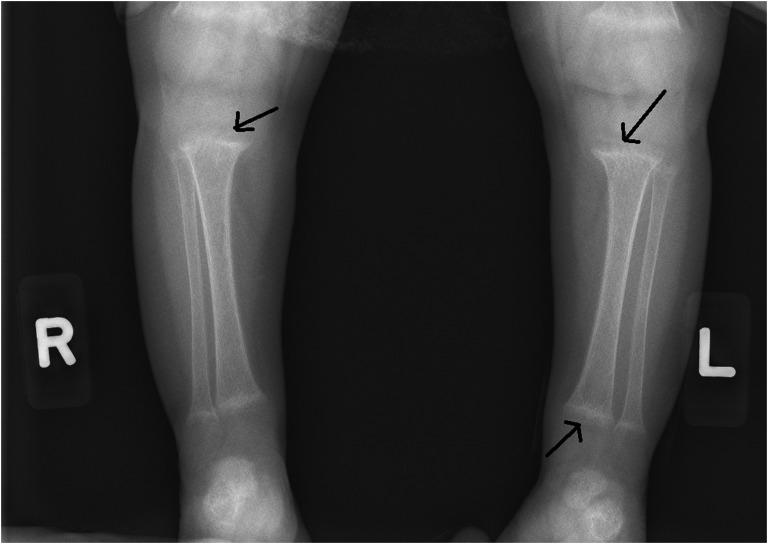

Vitamin D-deficiency rickets, not responding to large treatment doses of oral vitamin D, suggest rare receptor mutations, malabsorption, or hepatobiliary dysfunction. We present a set of twins of Hispanic origin who presented with refractory vitamin D-deficiency rickets and failure to thrive (FTT) at 6 months of age. On follow-up, mild elevations in serum alanine transaminases and normal aspartate aminotransferase were noted. Subsequently, patients manifested fat-soluble vitamin deficiencies. More targeted evaluations revealed a diagnosis of 3-hydroxy- -C-steroid oxidoreductase deficiency. Treatment with oral bile acid replacement with cholic acid resolved rickets and promoted weight gain. Bile acid synthesis disorders should be suspected in refractory rickets in infancy, particularly in a clinical setting of FTT, even in the absence of substantial abnormalities in liver-function tests.

对大剂量口服维生素D治疗无反应的维生素D缺乏性佝偻病,提示存在罕见的受体突变、吸收不良或肝胆功能障碍。我们报告了一组西班牙裔双胞胎,他们在6个月大时出现难治性维生素D缺乏性佝偻病和生长发育迟缓(FTT)。随访时,发现血清丙氨酸转氨酶轻度升高,天冬氨酸转氨酶正常。随后,患者出现脂溶性维生素缺乏。更有针对性的评估显示诊断为3-β-羟基-C27-类固醇氧化还原酶缺乏症。用胆酸进行口服胆汁酸替代治疗可治愈佝偻病并促进体重增加。对于婴儿难治性佝偻病,尤其是在生长发育迟缓的临床背景下,即使肝功能检查无明显异常,也应怀疑胆汁酸合成障碍。